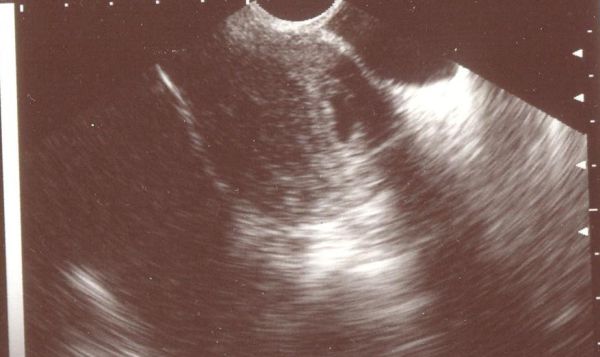

Első UH vizsgálat (5+1)

Első UH vizsgálat (5+1)

Második UH vizsgálat (8+1)

Második UH vizsgálat (8+1)